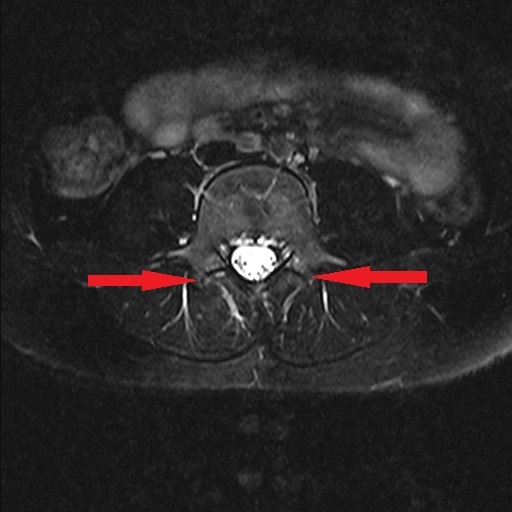

4月 MRI検査にて腰椎分離症の診断。コルセット装着の保存療法にて安静加療の指示。

6月 再検査。腰椎分離症の進行が見られた。

9月 再検査。変化なし。ボルトで脊椎を固定する手術(脊椎固定術)を打診される。

10月15日 再検査にて分離部位の癒合が認められるとの所見。

11月15日 再検査にて更に分離部位の癒合が認められるとの所見。現時点で腰痛や下肢疼痛など症状の再発は無し。

今回ご紹介する症例は、半年もの間一向に改善しなかった腰椎分離症がわずか1ケ月半の間に、しかも4回の施術で劇的な改善が見受けられたことについて、病院での一連の検査が終了した後に受療者の保護者より病院での検査記録の提供を受け、発症から治癒に至るまでの詳細について時系列でお伝えするものす。また、この症例はこれらの画像提供を受ける2ヶ月前の段階で既に筋肉反射テストにより損傷部位を正確に特定し、骨の癒合を促す施術を行った結果です。この目まぐるしい回復に専門医も只々驚愕しきりだったとか。本人は手術を受けるつもりでいたようですが、我が子の体にメスを入れることを良しとしなかった母親の慈愛が正しい選択に向かったのでしょう。CTやMRIは最先端の医療検査と思われがちですが、残念ながら損傷が分ったとしてもそこには回復させる術はありません。正しい検査のみが治癒の道筋を着けることを可能とします。体は常に自力で治ろうとして様々な症状を発現しています。体の訴えに耳を傾ける時、きっと自身の治癒力が成せる奇跡のような回復劇が待っていることでしょう。当院の施術には何のリスクもありません。手術を受ける前に是非ご相談ください。